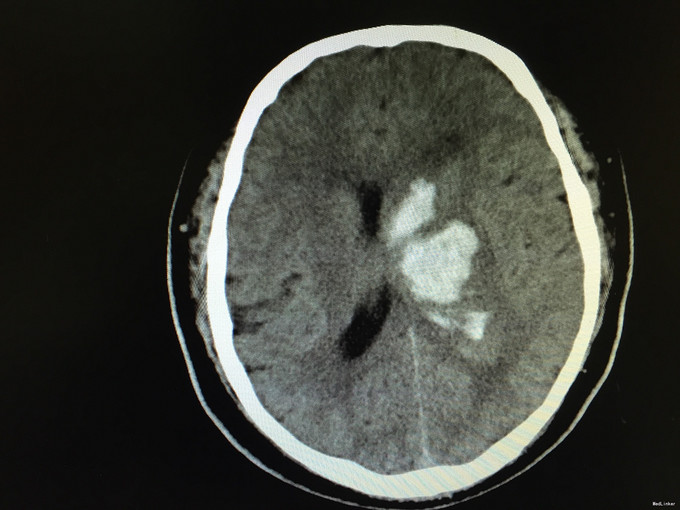

查体:右侧“三偏征”明显(偏瘫、偏身感觉障碍、偏盲),右病理征可疑阳性。 辅助检查:急诊行头颅CT,如下图,左侧基底节区出血。

诊断:脑出血 高血压3级(极高危) 治疗:安静卧床、脱水降颅压、冰帽降低脑组织代谢、调整血压、止血治疗等。